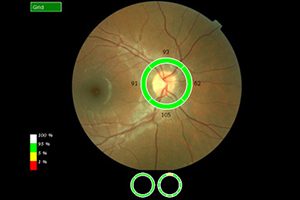

Nervenfaseranalyse (OCT)

Die Untersuchung am OCT ist ähnlich einem Foto ohne Blitz und dauert nur wenige Minuten. Sie erfolgt absolut schmerzfrei und ohne Berührung der Augen. Die Netzhaut wird um den Sehnerven durch ein Laserverfahren in optische Schnitte zerlegt und es kann damit wie bei einem mikroskopischen Gewebeschnitt die Netzhaut des Auges beurteilt werden. Das OCT führt eine objektive Messung der Nervenfaserschicht durch, da es keine Mitarbeit des Patienten verlangt. Das OCT zeigt frühzeitig ein Glaukom an, sogar wenn das Sehvermögen noch nicht beeinträchtigt ist.

Bei ca. 9-15 monatigen Folgeuntersuchungen kann dann ein Fortschreiten bzw. Stillstand bei entsprechender Therapie festgestellt werden.

Bei allen Vorteilen birgt die Methode aber den Nachteil, dass diese Untersuchung keine kassenärztliche Leistung ist und somit vom Patienten selbst getragen werden muss. Durch Sparzwänge in unserem Gesundheitssystem ist es z. Zt. fraglich, ob diese Methode in den Leistungskatalog der GKV aufgenommen wird.

Ausdruck OCT: normale Papille mit normaler Nervenfaserschicht

Sehnervenfaseranalyse